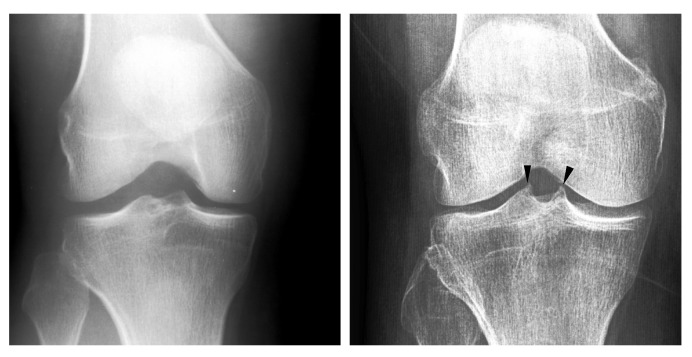

有效的和可扩展的早期诊断方法的膝关节骨关节炎是需要的,由于疾病的患病率。目前使用x线平片自动检测骨关节炎的方法难以识别早期疾病的受试者。胫骨刺突被认为是早期膝骨关节炎的特征。先前的研究已经证明膝关节骨性关节炎和胫骨刺突之间存在关联,但与早期疾病的关系尚未被调查。我们研究胫骨刺突作为早期膝骨关节炎的一个特征。此外,我们开发了一种基于深度学习的模型,用于从x线平片中检测胫骨尖峰。我们收集了913张胫骨刺突的膝关节x线片并进行了分级。我们进行了两个实验:实验A和实验b。在实验A中,我们使用Mann-Whitney U-test对有胫骨刺突和没有胫骨刺突的受试者进行比较。实验B包括开发和验证一种基于解释性深度学习的预测胫骨刺突的方法。胫骨刺突的受试者有更严重的kelgren - lawrence分级,内侧关节间隙狭窄,胫骨外侧腔室骨赘评分。该方法的准确度为0.869。我们发现胫骨刺突是膝关节骨关节炎诊断的一个有希望的特征。此外,检测可以自动化。

Efficient and scalable early diagnostic methods for knee osteoarthritis are desired due to the disease's prevalence. The current automatic methods for detecting osteoarthritis using plain radiographs struggle to identify the subjects with early-stage disease. Tibial spiking has been hypothesized as a feature of early knee osteoarthritis. Previous research has demonstrated an association between knee osteoarthritis and tibial spiking, but the connection to the early-stage disease has not been investigated. We study tibial spiking as a feature of early knee osteoarthritis. Additionally, we develop a deep learning based model for detecting tibial spiking from plain radiographs. We collected and graded 913 knee radiographs for tibial spiking. We conducted two experiments: experiments A and B. In experiment A, we compared the subjects with and without tibial spiking using Mann-Whitney U-test. Experiment B consisted of developing and validating an interpretative deep learning based method for predicting tibial spiking. The subjects with tibial spiking had more severe Kellgren-Lawrence grade, medial joint space narrowing, and osteophyte score in the lateral tibial compartment. The developed method achieved an accuracy of 0.869. We find tibial spiking a promising feature in knee osteoarthritis diagnosis. Furthermore, the detection can be automatized.